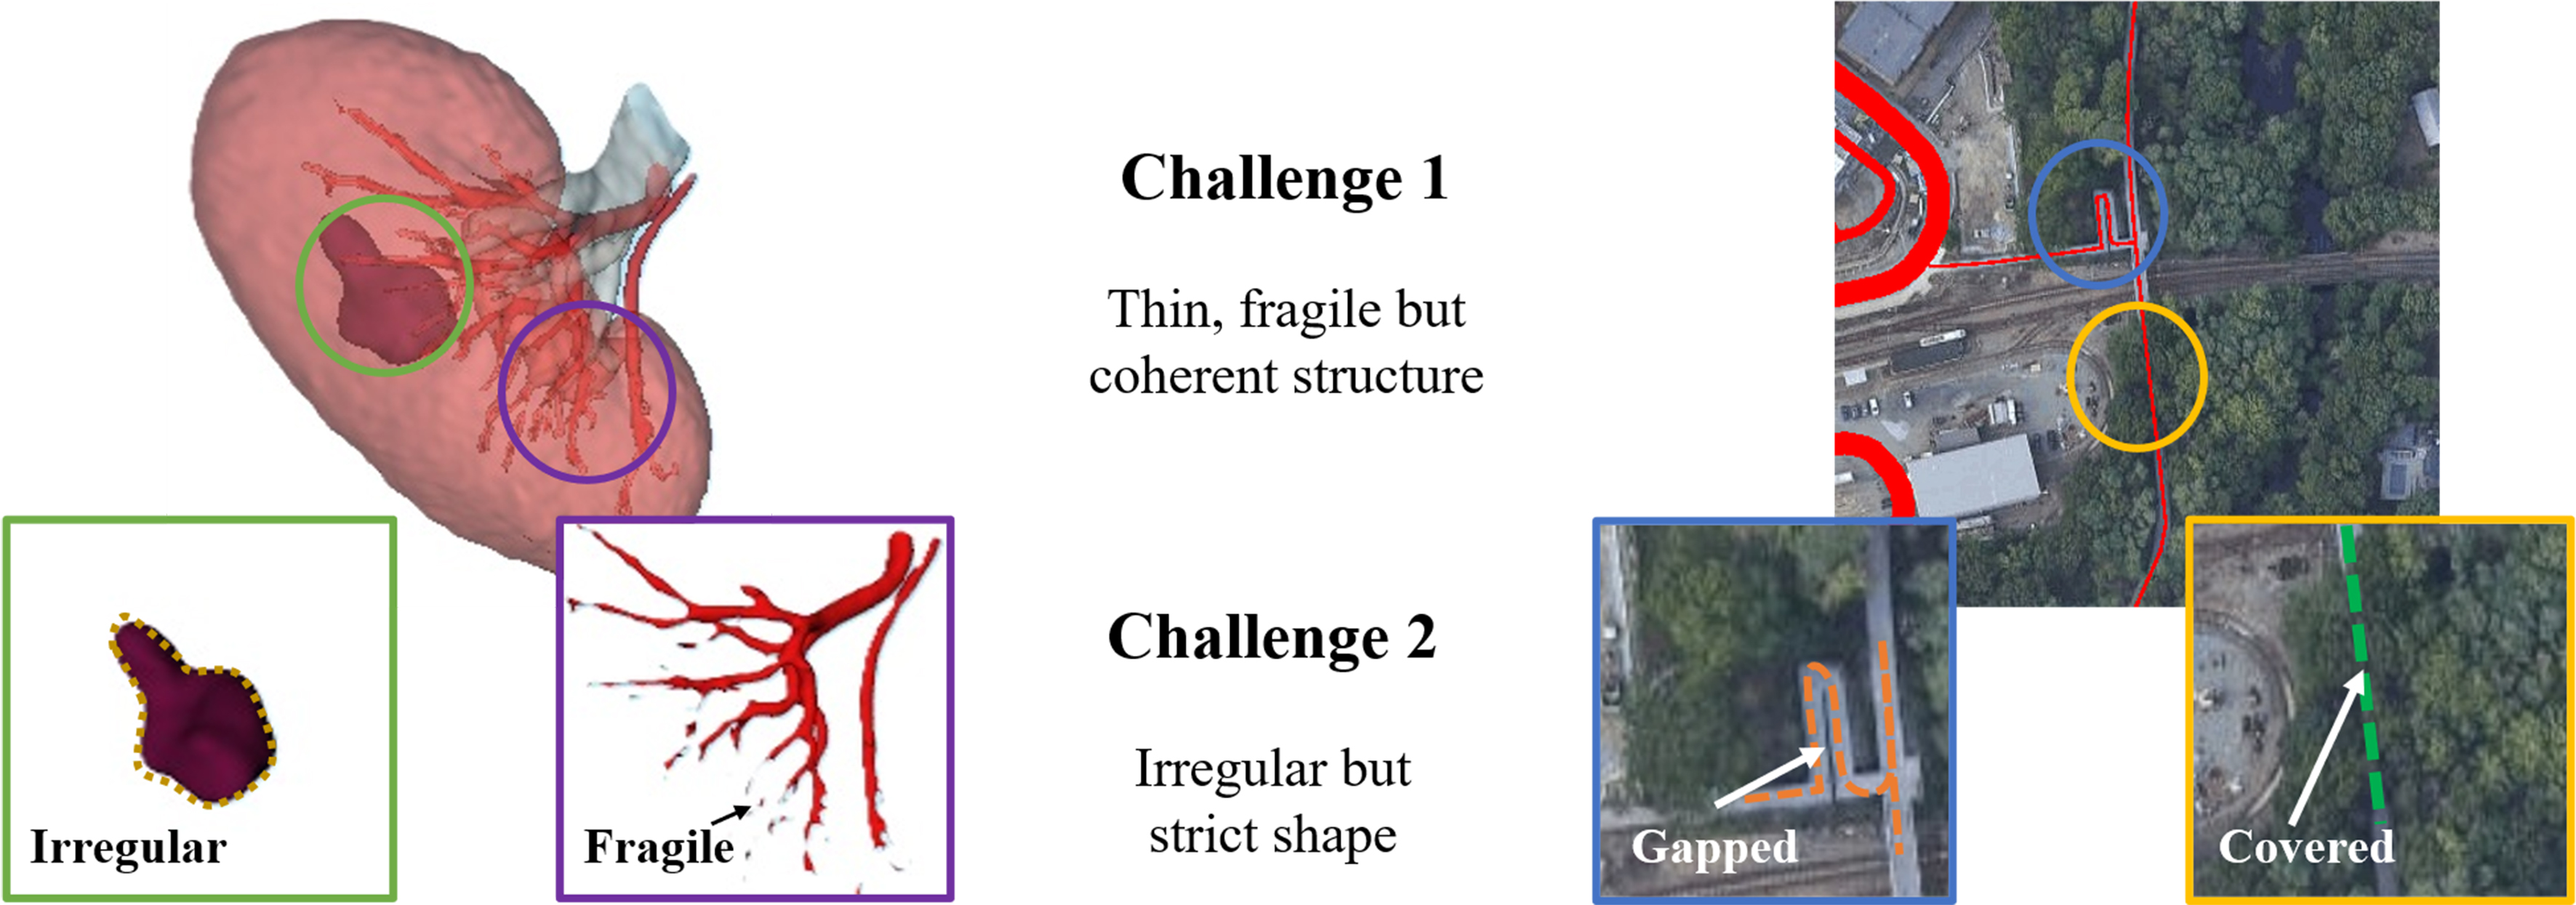

For the above structure, we face many challenges when performing segmentation, as shown in Figure 1. Taking blood vessels as an example, their narrowest part is only 2-3 mm, occupying only a small number of pixels in the image, which is easily overlooked in the segmentation process. In addition, although these structures require high continuity, the impact of occlusion or small gaps cannot be ignored.

The current problems in the segmentation of slender structures mainly include the following aspects. First, for slender structures, due to their small number of pixels, traditional convolution operations may be affected by complex backgrounds, resulting in limited feature recognition. Especially when all parts of the image share the same convolution weight parameters, some structures with special shapes may be submerged as a result. Second, due to the fixed and regular calculation method of convolution, it cannot achieve adaptive and coherent feature extraction along slender structures. Third, especially in U-Net structured networks, multiple downsampling operations may cause the original pixels to fold or overlap, making them difficult to distinguish. Besides, in the training process of multi classification tasks, the loss function does not pay sufficient attention to the slender structures with fewer pixels, which causes class imbalance and affects the overall training process.

In addition, the segmentation ability of slender structures also represents the network’s ability to understand topological features. In segmentation tasks such as tumors that require strict requirements for morphological features and contour extraction, the ability to adaptively extract contours is particularly important.